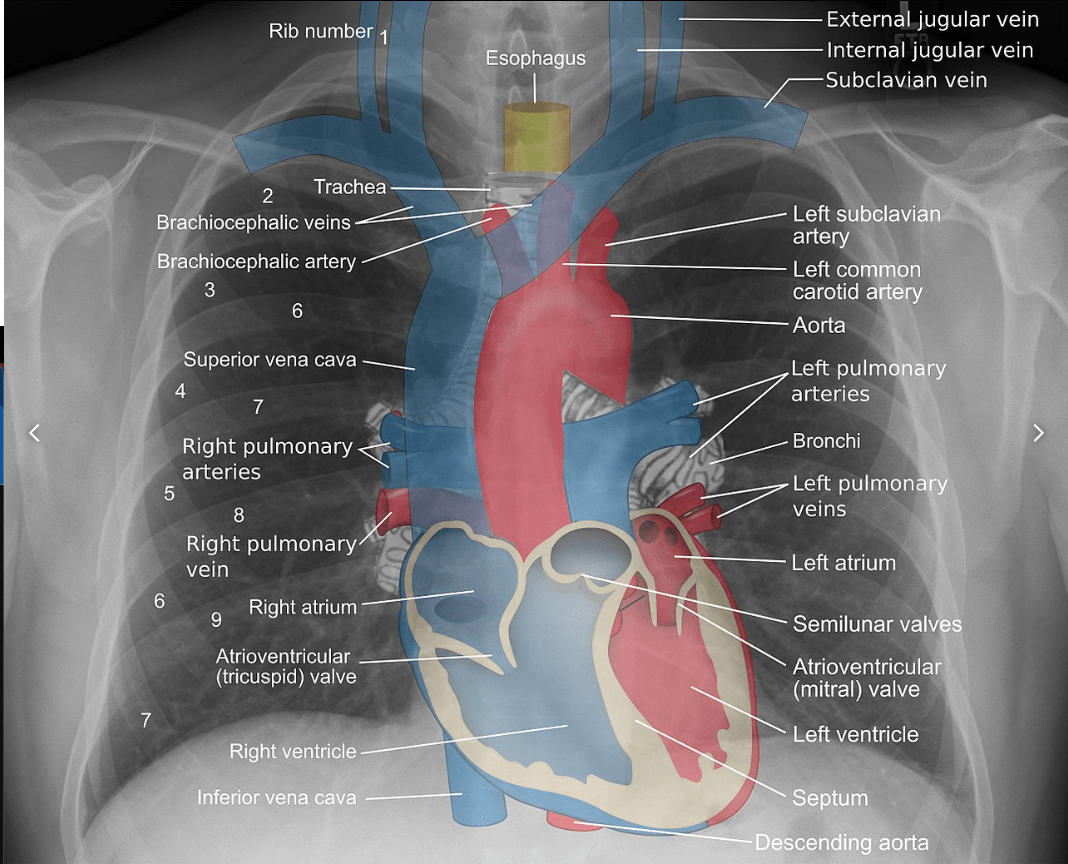

Chest Radiographs

• Visualizes the lungs

• Visualizes the heart

Radiologists have a very strong mental model of what a CXR should look like